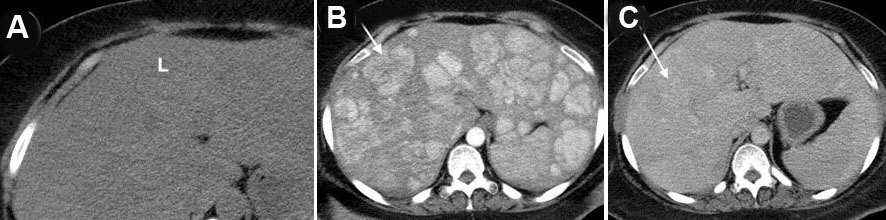

A 33-year-old black female with a past medical history of seizures, hypertension, type-2 diabetes, cognitive impairment, and neuropathy resulting in complete loss of ambulation was referred to our institution for radiologic evaluation following an abnormal liver function test (alkaline phosphatase (ALP) 1193; alanine transaminase/aspartate transaminase (ALT/AST) were normal at 16/16 U/L), microcytic anemia, and a vitamin B12 deficiency. No alcohol, drug, tobacco use, or family history of liver disease were noted. On physical exam, jaundice and abdominal pain were absent; chronic fatigue had been present for several months. Abdominal ultrasound (Figure 1A and Figure 1B) revealed hepatomegaly that exceeded 23 cm, with multiple heterogenous masses in both lobes of the liver hyperechoic to the surrounding parenchyma; further evaluation with contrast-enhanced CT (Figure 2A, Figure 2B, Figure 2C) revealed enhancement of approximately 100 lesions throughout both liver lobes, the largest measuring 5–6 cm. The liver parenchyma had a uniform density without pathologic enhancement and a normal gallbladder without evidence of biliary dilation. Magnetic resonance imaging (MRI) (Figure 3A, Figure 3B, Figure 3C) shows numerous T2 hyperintense hepatic lesions, which enhanced during the arterial phase with intravenous (IV) gadolinium. To rule out a hyper-vascular primary malignancy or vascular metastasis, a CT-guided percutaneous biopsy of the liver was performed. Pathology identified mild macro-vesicular steatosis and marked sinusoidal dilation (Figure 4A, Figure 4B, Figure 4C), consistent with peliosis hepatis and mild macro-vesicular steatosis of the liver. Occult bleeding of the upper and lower gastrointestinal tract (GI) tract was ruled out; the anemia was treated with Vitamin B12 injections and IV iron transfusions. After two years of follow-up, the anemia persisted; testing revealed alfa-thalassemia minor. Radiographic follow-ups noted stable lesions; the patient has remained asymptomatic three-years post-diagnosis. Interestingly, however, the patient’s lab values have continued to show elevated ALP levels that vary between 1200 and 1700 IU/L, while the ALT/AST values have remained normal.

Figure 2: (A) Non-contrast, (B) arterial phase, and (C) portal venous phase intravenous contrast enhanced computed tomography of the abdomen shows multiple enhancing liver lesions in the arterial phase (one example noted with white arrows) that are not clearly delineated without intravenous contrast (A) and less conspicuous in the venous phase (A). L=liver, S=spleen.

Diagnostic imaging is essential in evaluating PH due to biopsy/surgery bleeding risk. Initial ultrasound (55.6%; n=35) identified homogenous/hypoechoic lesions with hepatic steatosis or hyperechoic lesions with normal hepatic parenchyma [16],[26], as noted in our patient (Figure 1). Doppler studies can identify blood flow and thrombi or portal obstruction [6],[16],[26]. Contrast-enhanced CT (54.0%; n=34), the preferred imaging modality [4],[16],[18],[26],[32],[33],[34], differentiates hypoattenuating peliotic lesions versus normal parenchyma [16],[18],[32],[33],[34],[35]; characteristically, early central enhancement during the arterial phase with centrally accumulating contrast in a “target sign” that diffuses to the periphery during the venous phase is noted in PH [16],[18],[26],[33],[34],[35]. With an active hemorrhage, hyperattenuating contrast material may accumulate or leak during the late phase [4],[16],[18],[26],[32],[33],[34]. The initial CT in our report revealed multiple enhancing lesions throughout the liver parenchyma, the largest 5–6 cm (Figure 2).